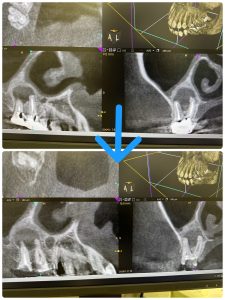

ヤグレーザー‼️だね、

また3カ月後が楽しみだ

来年5月にはMTA根充予定

ヤグレーザーは、既存の概念を覆す程の威力だ!

常に考えながら、試行錯誤が良い発想をもたらす